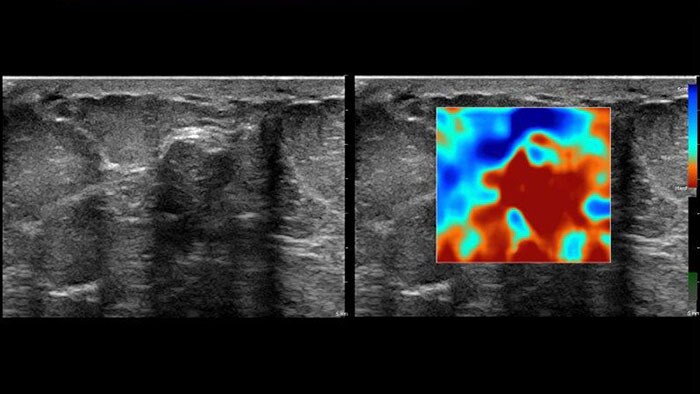

US Q-App Elastography Analysis (EA)*

Explore new tissue stiffness measurements

US Q-App Elastography Analysis (EA)* allows you to strain elastography analysis of tissue deformation based on an elastogram. The applications can be used to size compare between two ROIs; results may be appended to patient reports.

Benefits

- Thumbnail display of frames.

- Size comparison between two ROIs.

- Strain ratio calculation.

- Append to patient exam.

- Compatible with Philips EPIQ, Affiniti and iU22 systems using Elastography mode.

* Only available for sale in the US.